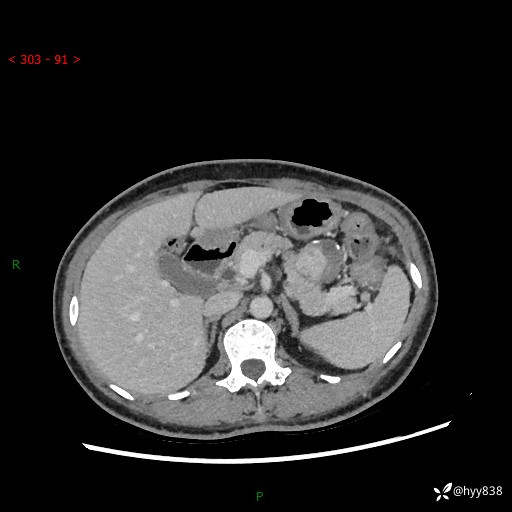

增强动脉期+静脉期

img